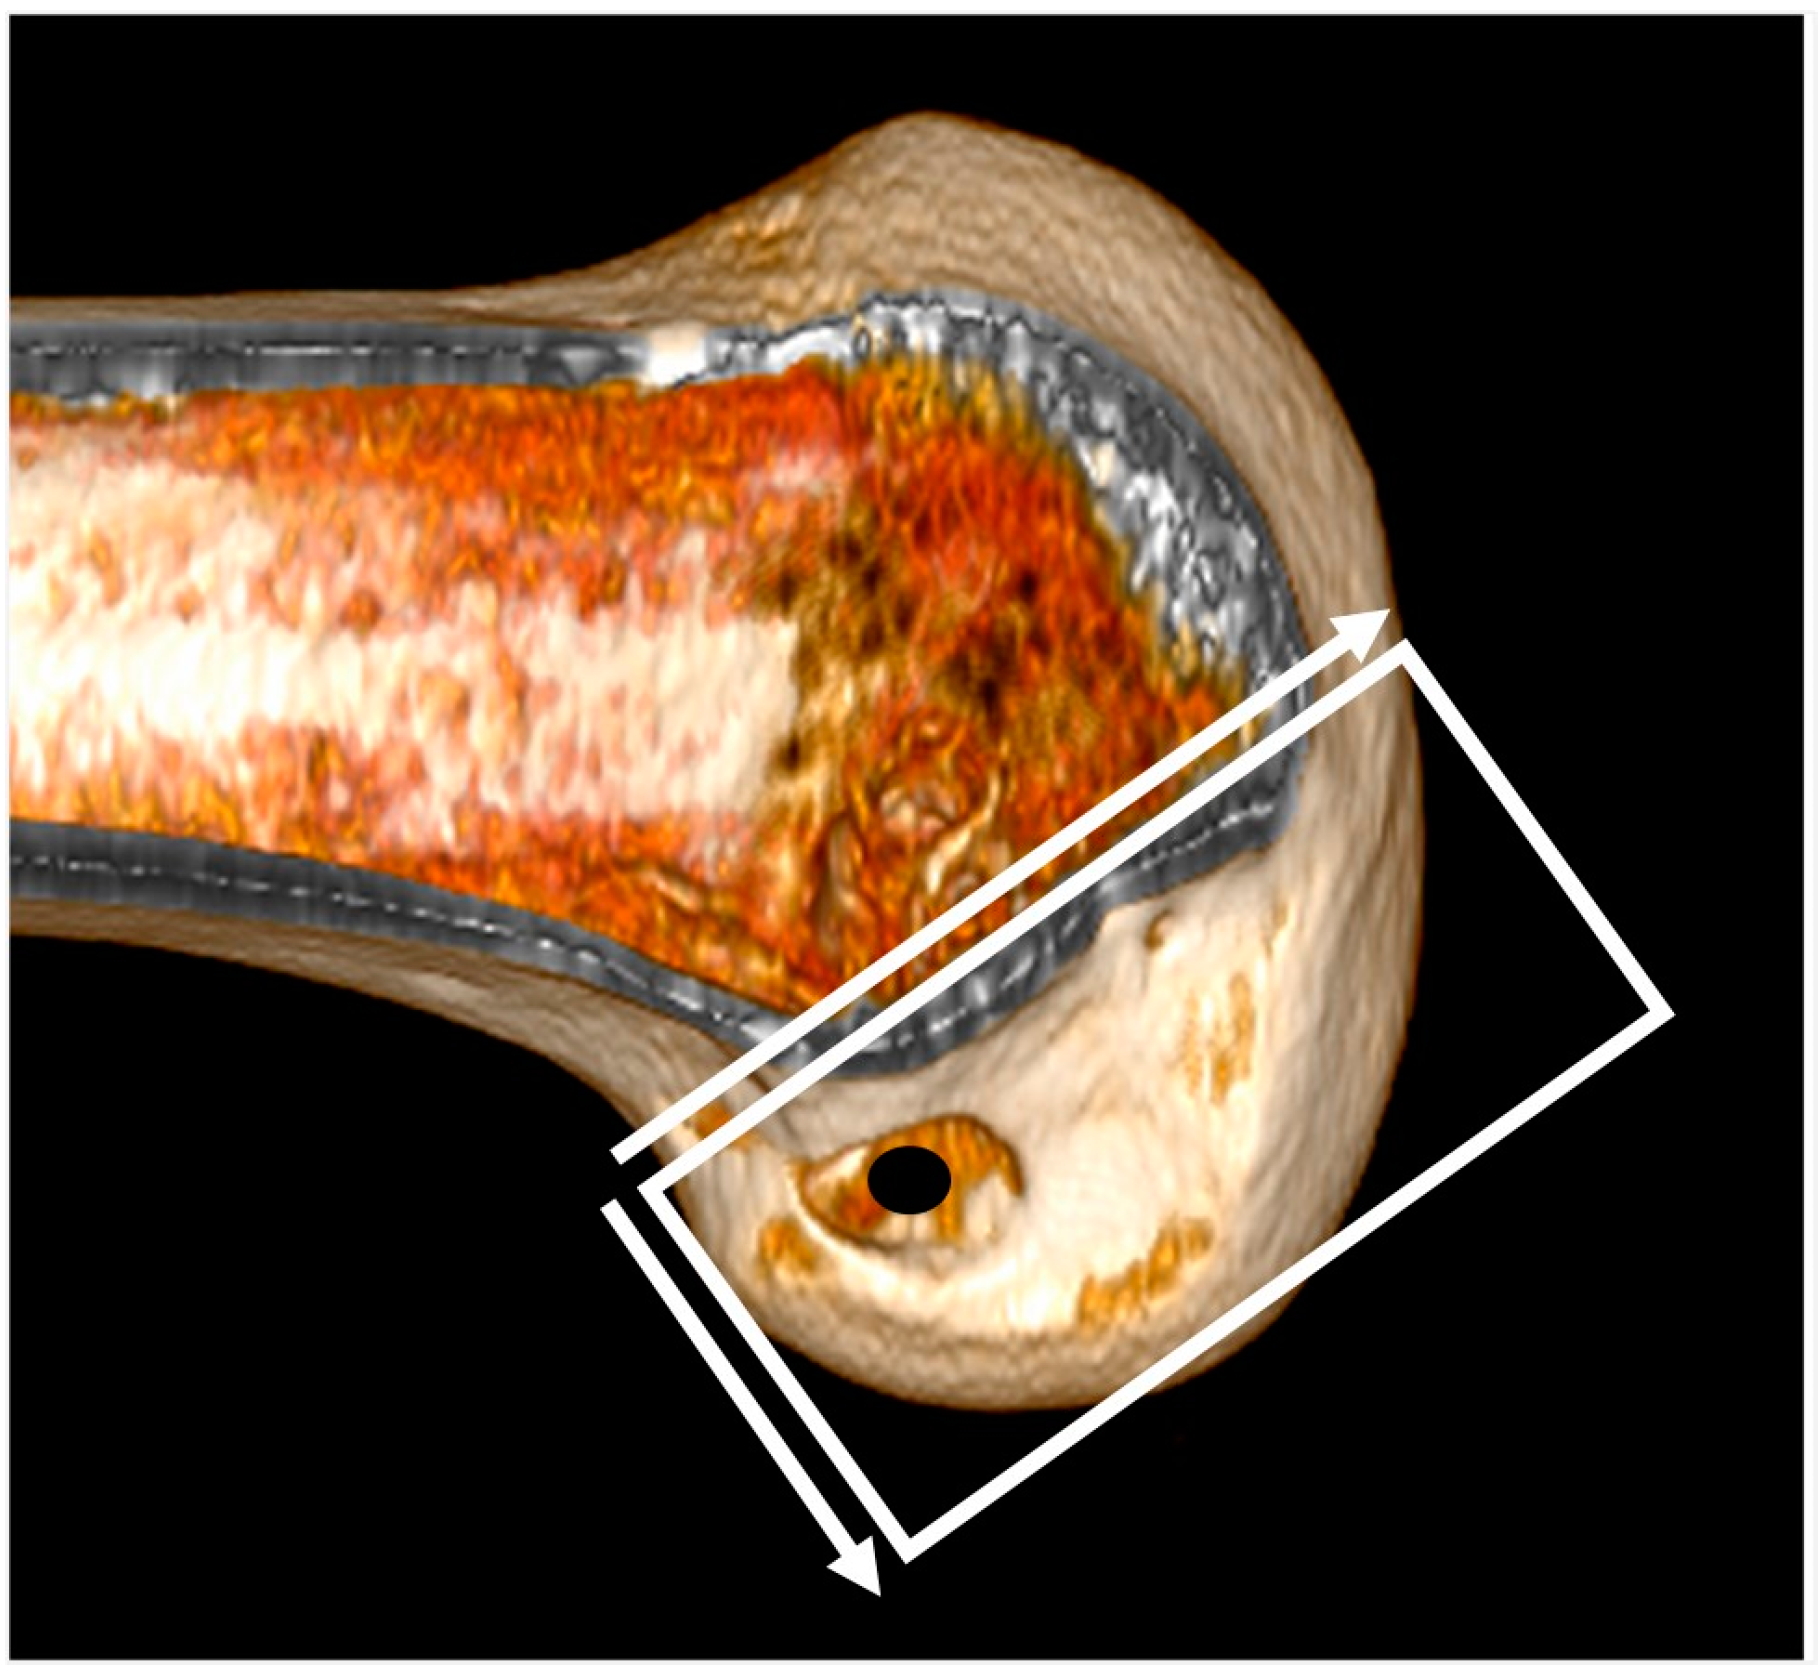

The 3D CT scans were imported into 3D software (AW Sever 3.2 PACS system, GE Healthcare; Chicago, IL, USA) for the assessments of the femoral graft bending angle and femoral tunnel length. The femoral graft bending angle was defined as the angle formed by the longitudinal axis of the femoral tunnel and the line connecting the intra-articular aperture of the tibial tunnel and the intra-articular aperture of the femoral tunnel (Figure 3). The femoral tunnel length was defined as the distance between the center of the extra-articular aperture of the femoral tunnel and the center of the intra-articular aperture of the femoral tunnel in a plane where the entire femoral tunnel could be viewed (Figure 4). Posterior wall breakage of the femoral tunnel was also checked.

Figure 4. The femoral tunnel length is defined as the distance between the center of the extra-articular aperture of the femoral tunnel and the center of the intra-articular aperture of the femoral tunnel.